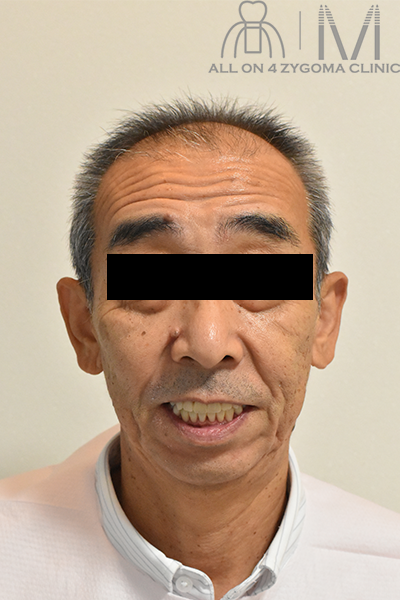

最終補綴物セット後の顔貌所見

顔貌はほぼ左右対称、リップサポートを認め、上唇は自然な豊隆を認める。スマイルラインは下唇上部に沿うような湾曲を描いている。

上顎正中は顔貌の正中に一致している。